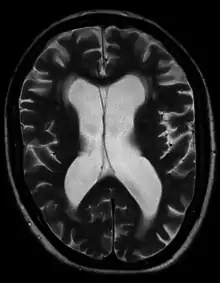

Hydrocephalus as seen on a CT scan of the brain. The black areas in the middle of the brain (the lateral ventricles) are abnormally large and filled with fluid.